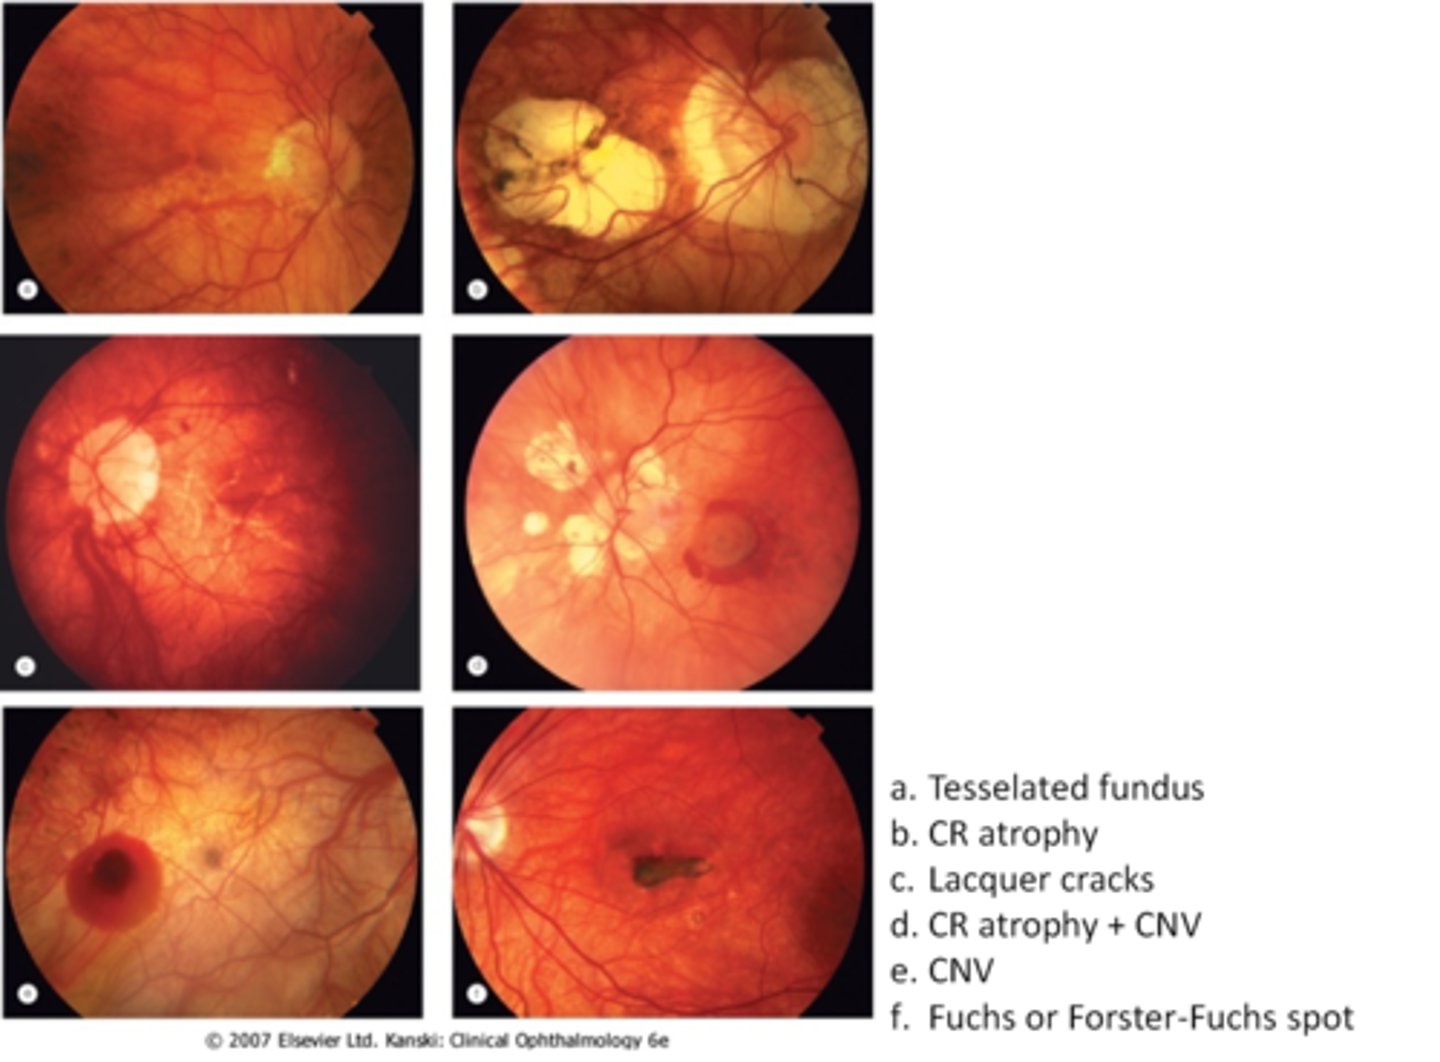

tesselated or tigroid fundus = visibility of choroidal vasculature (A)

What are some common findings in degenerative myopia?

lacquer cracks (C)

CNV (E)

chorioretinal atrophy (B)

What findings of degenerative myopia are seen here?

PPA

crescent

lacquer cracks

How do lacquer cracks appear on fundoscopy?

jagged, irregular yellow lines showing sclera in the posterior pole